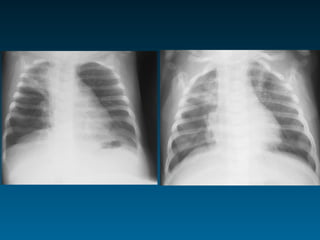

Παθολογικές σκιάσεις εκτός παρεγχύματος

Παθολογικές διαυγάσεις εκτός παρεγχύματος